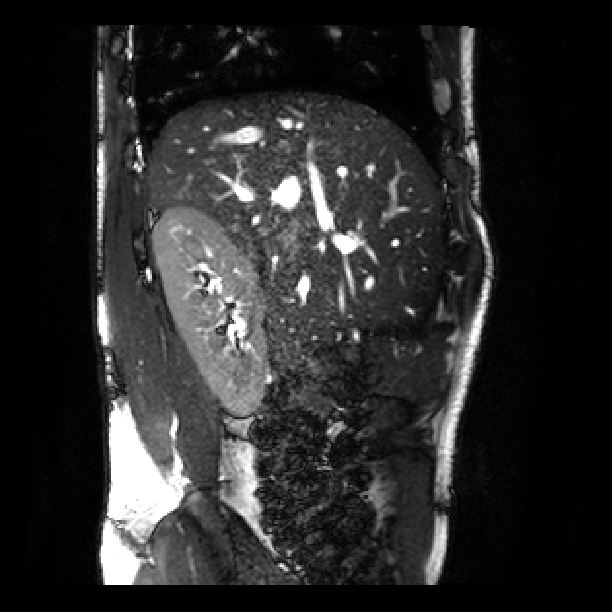

Fig. 3 shows a similar comparison for abdominal MRI of a pregnant patient. As highlighted in the red box, where the artifact is caused by a deep breath, due to lack of a good target with only one stack of 2D MR images, the state-of-art SVR method failed in the area with large motion corruption.

![]() |

| (a) | (b) | (c) |